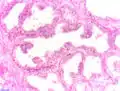

Adénocarcinome prostatique

Adénocarcinome ; tissus indifférenciés

Invasion périneurale par un adénocarcinome prostatique. HE, x400

Score de Gleason

La structure tissulaire des cancers de la prostate varie des formes différenciées (cellules cancéreuses ressemblant aux cellules saines), dite de grade 1, aux formes les moins différenciées (cellules cancéreuses présentant beaucoup de caractères atypiques par rapport aux cellules saines), dite de grade 5.

Plusieurs grades peuvent se rencontrer au sein d'un même tissu. Le score de Gleason est calculé de la façon suivante : on additionne les deux grades les plus représentés de la tumeur. Le premier chiffre représentant le score du contingent le plus représenté. Ainsi 4+3 est plus péjoratif que 3+4

Si la somme est de 6 ou moins, le cancer est dit bien différencié, donc de meilleur pronostic ; 7 : le cancer est moyennement différencié ; 8 ou plus : le cancer est peu différencié, donc de moins bon pronostic.